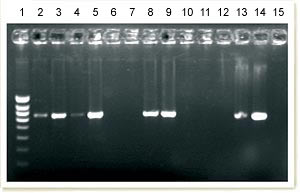

Gel issu de PCR conventionnelle pour la détection de l’ADN du PCV2. La colonne 1 correspond à l’échelle de poids moléculaire. On observe la présence d’ADN du PCV2 amplifié dans les colonnes 2, 3, 4, 5, 8, 9, 13 et 14. Les 13 et 14 correspondent aux porcs sains d’un élevage non atteint : ils fournissent une réponse de même intensité sur ce gel.

Ce qui montre que la PCR conventionnelle n’est pas une technique discriminante pour le diagnostic de la maladie.